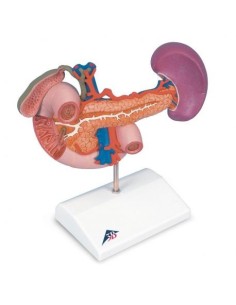

Dal cranio in 22 parti con incastri magnetici ai modelli di colonna vertebrale, da quelli di articolazioni a quelli di cuore, ogni pezzo della nostra collezione è progettato per un’immersione totale nello studio dell’anatomia umana. I nostri modelli, realizzati tramite scansioni di ossa vere, garantiscono un’esperienza tattile autentica e una fedeltà di peso quasi identica agli originali.

Essenziali per studenti e professionisti, i nostri modelli anatomici sono strumenti didattici che permettono di osservare le strutture anatomiche con precisione, eliminando la necessità di dissezioni o studi invasivi. Sono inoltre utili per spiegare ai pazienti le patologie, rendendo la comunicazione più efficace e risparmiando tempo prezioso.